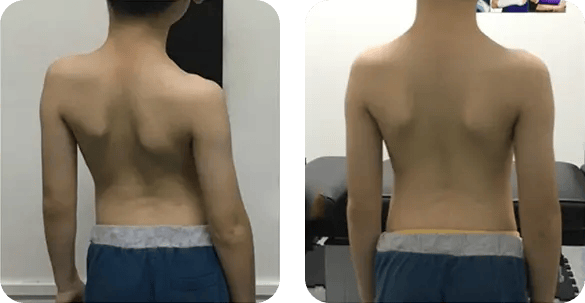

See the Results for Yourself

Real patients. Visible progress. Explore our success stories and before & after transformations that showcase the power of consistent chiropractic care and scoliosis bracing.

3 months of chiropractic care significantly improved spinal alignment.

Chronic posture issues resolved through targeted adjustments and scoliosis corrective exercises. The patient now stands taller with straight posture and better balance.